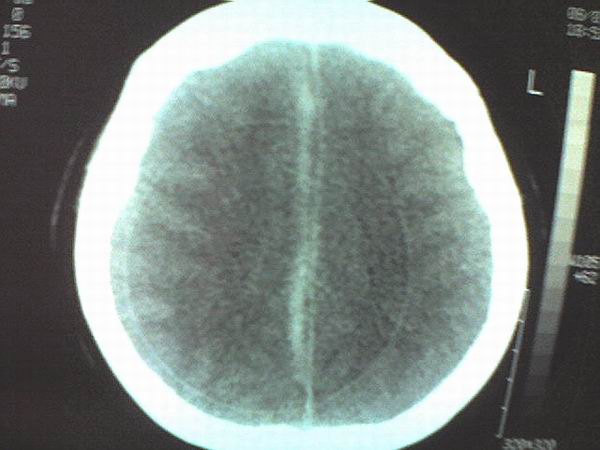

女 43岁 头痛恶心呕吐两天

手机照的,不是太清楚。

右侧大脑镰硬膜下出血

1、右侧大脑镰硬膜下出血2、机器伪影太重,该修修。